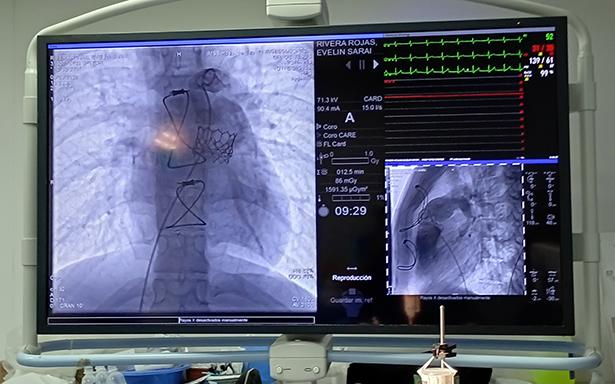

El jefe del Servicio de Hemodinamia de esta UMAE, doctor Alberto Bazzoni Ruiz, explicó que el pasado 6 de marzo, Evelin “N” de 18 y Luis “N” de 19 años, ambos de Durango, fueron los primeros pacientes en ser intervenidos con este procedimiento que se realiza mediante una punción en la vena femoral (ingle) como vía de acceso hasta el corazón, a fin de implantar la prótesis de la válvula que se va a reemplazar o reparar sin necesidad de abrir el tórax y exponer el corazón, como se hacía en el pasado.

En marzo de este año, el doctor Teodoro de Jesús Alvarenga, cardiólogo intervencionista con alta especialidad en cardiopatía congénita y un equipo multidisciplinario encabezado por el doctor Bazzoni Ruiz realizaron la colocación de válvula pulmonar transcateter a Evelin y Luis, procedimiento que se efectuó en menos de una hora en cada caso.